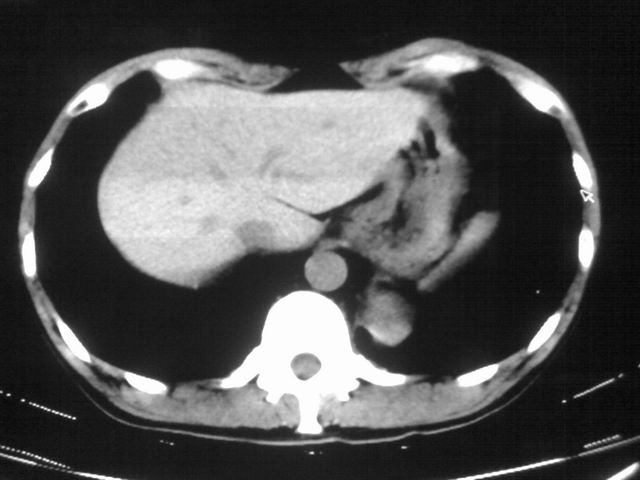

以下是引用苯小孩在2007-4-24 19:46:00的发言:[br]左下肺内侧基底段,见类圆形病灶,边缘清晰光滑.强化后轻中度强化.<平扫第4层面似有从腹主动脉相连血管影,可惜强化扫描这层没有抓住>考虑:左下肺隔离症.建议dsa或薄层强化重建观察.

以下是引用同在2007-4-24 20:11:00的发言:[br]考虑肺隔离症